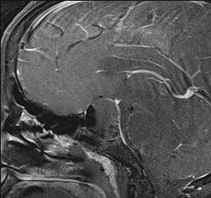

65 year old male with Pituitary Macroadenoma with cavernous sinus extension. Endoscopic Transsphenoidal Surgery done with Intraoperative MRI showing residual tumor in the cavernous sinus region under the left carotid artery. Post op MRI showing on the right no residual tumor in the sinus. (T1 contrast above and T2 coronal sections below).

- Pre-operative sagittal contrast enhanced T1W image shows a sellar mass with suprasellar extension (Figure 4)

- Intra-operative MRI (Figure 5) shows residual enhancing tumour, which was then taken up again for resection. Post operative MRI (Figure 6) shows a thin enhancing capsule with no residual tumour.